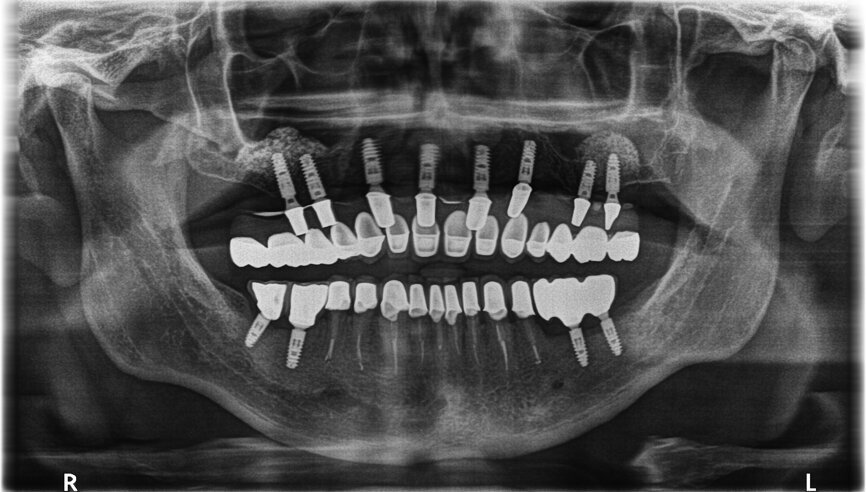

Fig. 30: OPG after placing implants.

Fig. 31: OPG after exposing implants at the lateral section and having used a temporary prosthesis based on telescopes.

Fig. 32: OPG after treatment.

If the quality of the work satisfies our expectations, we may proceed to the handing-over stage and perform the functional and aesthetic analysis, both intra- and extraorally. A perfect conclusion to the treatment process is the receipt of a complete set of OPG X-rays taken before, during and following treatment (Figs. 29–32).